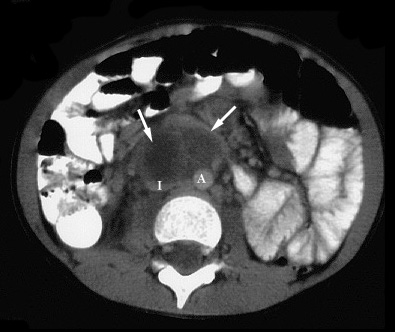

Figure 1. Axial CT image of the pelvis shows a soft tissue mass (arrows) posterior to the bladder (B) |

Figure 2. Axial CT image of the lower abdomen (same patient as 1.) shows a hypodense mass (arrows) with an enhancing rim anterior to the inferior vena cava (I) and aorta (A) resembling a mesenteric abscess. The inferior vena cava is compressed by the mass. |